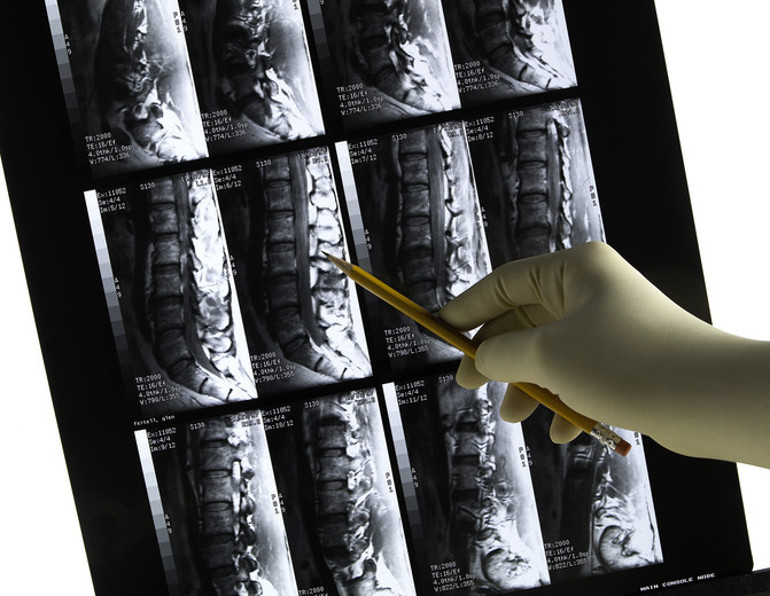

Skolyoz çoğu zaman dikkatli bir gözle fark edilebiliyor. Omurgaya arkadan bakıldığında bazı eğrilikler düz durulduğunda net olarak görünmese de çocuk öne eğildiğinde, yapılan kontroller veya röntgen filmleriyle kolayca tespit edilebiliyor.

Skolyoz, omurganın göğüs veya bel bölgesinde yana doğru eğrilmesi durumudur. Sağlıklı bir omurga arkadan bakıldığında boyun, sırt ve bel boyunca düz bir çizgi oluşturur. Skolyozda ise omurlar yana kayar ve kendi eksenleri etrafında döner; bu da sırt ve duruşta belirgin asimetriye yol açar. Erken fark edildiğinde tedavi ve egzersizlerle ilerlemesi önlenebilir, bu nedenle ailelerin çocuklarının duruşunu düzenli olarak gözlemlemesi önemlidir.